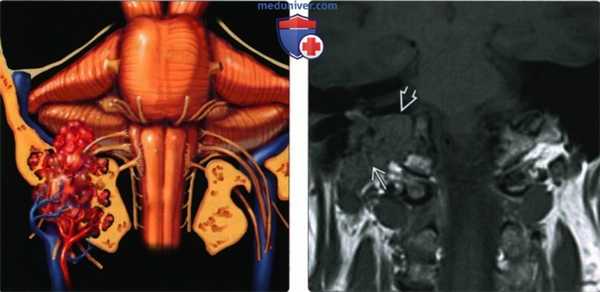

(Слева) На рисунке коронального среза показана крупная параганглиома яремного гломуса, возникшая в яремном отверстии; опухоль инфильтрирует соседние структуры основания черепа, она поглотила яремную вену и ЧН IX-XII.

(Справа) При МРТ Т1ВИ в корональной проекции определяется крупная параганглиома яремного гломуса, проросшая основание черепа и распространяющаяся вверх и латерально к наружному слуховому проходу. Обратите внимание на множественные «пустоты потока» из-за высокой скорости кровотока, характерные для параганглиомы. Параганглиома яремного гломуса - вторая по частоте опухоль височной кости.

(Слева) При MPT Т2 ВИ в аксиальной проекции определяется крупное новообразование, исходящее из яремного отверстия; в ткани образования определяются множественные «пустоты потока» вследствие высокой скорости кровотока. Такая картина помогает дифференцировать эту опухоль от других новообразований этой зоны. Также наблюдается экссудация в ячейки пирамиды височной кости, вызванная обструкцией евстахиевой трубы.

(Справа) Корональная МРТ Т1ВИ FS с КУ: контрастная параганглиома яремного гломуса, прорастающая основание черепа и распространяющаяся кверху и латерально к среднему уху и наружному слуховому проходу. Этот пациент 15 лет с мутацией SDHB находится в группе высокого риска развития агрессивной параганглиомы.